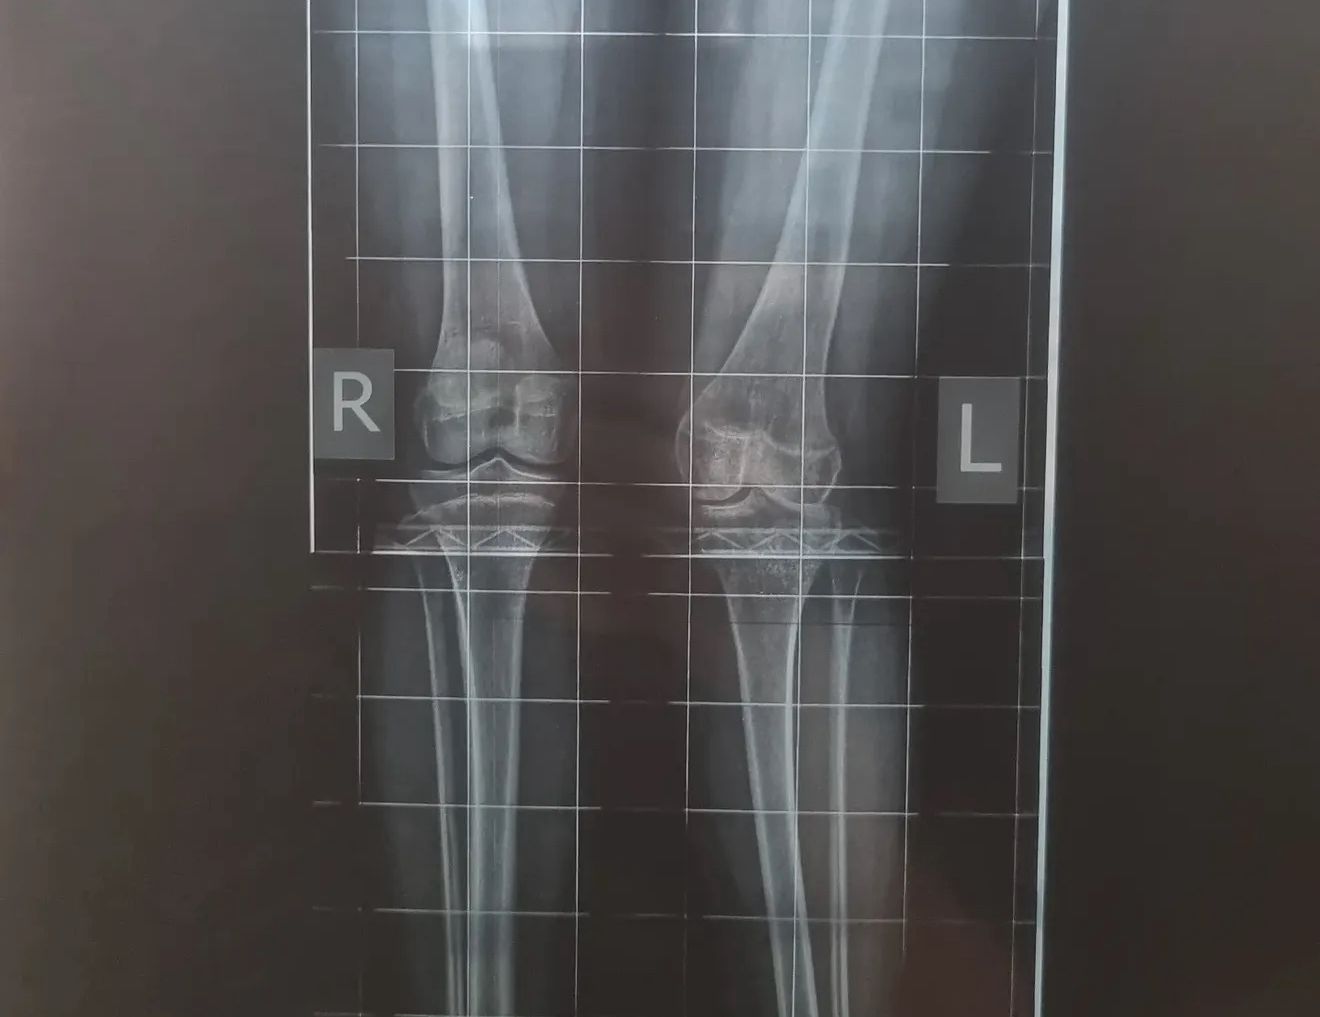

Однако на этом борьба не закончилась. На протяжении трех лет петропавловцы регулярно ездят в Курган на контрольные осмотры. Из-за ограниченной подвижности тазобедренного сустава у Юли развилась вальгусная деформация колена и костей голени. Врачи рекомендуют провести новую операцию как можно раньше, чтобы избежать серьезных осложнений, в том числе артроза.